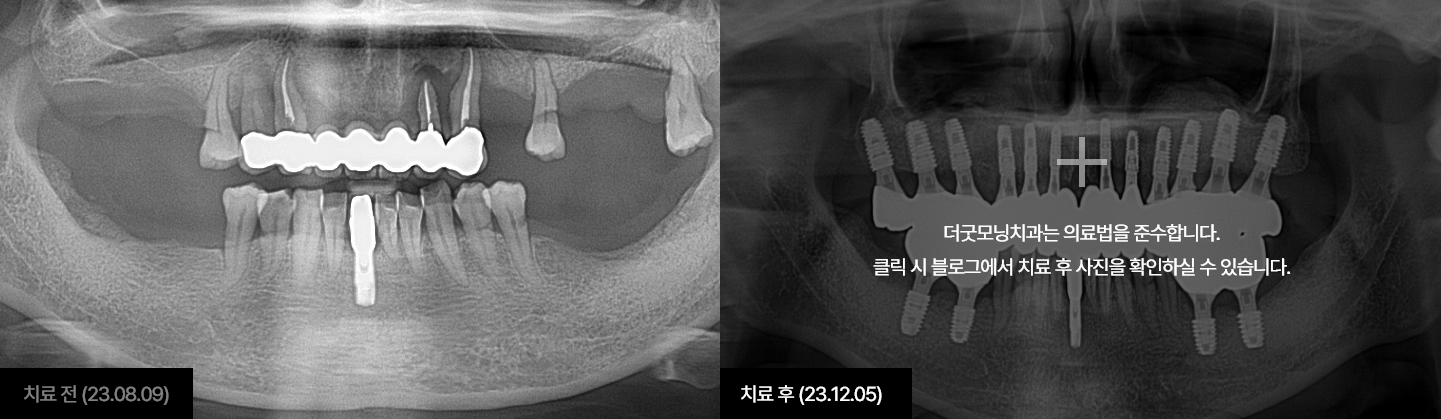

더굿모닝치과는 실제 수술 전, 3차원 3D-CT를 이용하여

정밀진단과 가상수술을 통해 임플란트를 식립할 위치, 방향, 깊이 등

환자 개인의 수술 조건을 사전에 파악하여

한 치의 오차 없이 정확하고 빠르게 완성합니다.

아무리 완벽한 치료와 좋은 재료여도 가장 좋은 것은 자연치아입니다.

개인의 구강상태를 고려하여 가장 적합한 보철물을 통해

치아의 기능적 회복 및 심미적인 부분까지 개선하는 치료입니다.